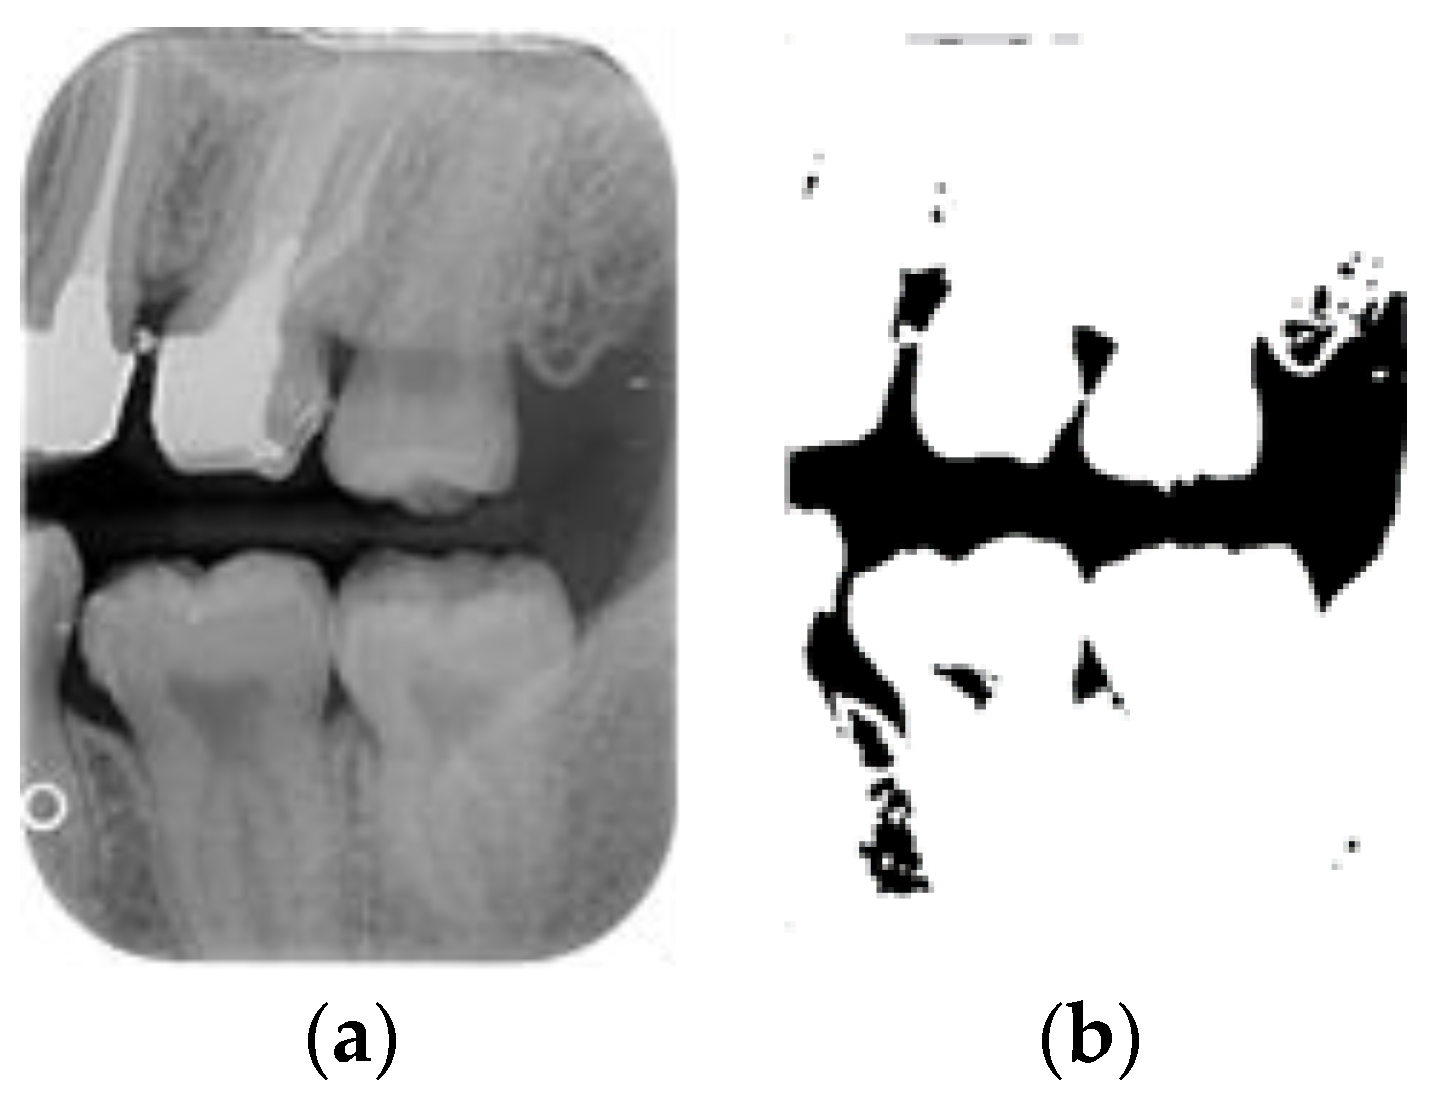

Figure 8.

Image-enhancement results: (a) binarization; (b) mathematical morphology; (c) added green line represents canny; (d) overlap onto the original image.

2.3.5. Canny Edge Detection

Since filtered and binarized images alone cannot enhance the features of dental calculus, this approach does not effectively improve the accuracy of machine learning. Therefore, this study employed edge detection to identify the contours of tooth edges, enhancing the regions of interest and thereby improving the accuracy of machine learning. The canny edge-detection algorithm applies non-maximum suppression to each pixel, retaining pixels with local maximum gradient values, which can produce continuous and accurate edges while demonstrating good resistance to noise. The edge-detection results are represented in green, as shown in Figure 8c. Finally, these results are overlaid back onto the original image, as illustrated in Figure 8d.